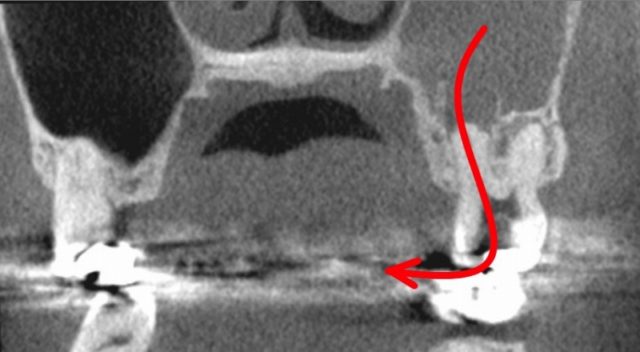

顔が痛い 頬骨も痛い とき 治療 根管治療

上で根管長測定した長さで、

根管を掃除します。

できれば、

歯の内部から、上顎洞まで、

開通させます。

顔が痛い 頬骨も痛い とき 根管治療 排膿

上顎洞内の膿は、

歯の内部から、膿を吸い出すこともできます。

この様に、根管治療し、

顔や頬骨が痛い事もなくなりました。

今回の急性上顎洞炎の原因は、

大きな虫歯治療の後、

神経が死んで、根管が化膿したためでした。